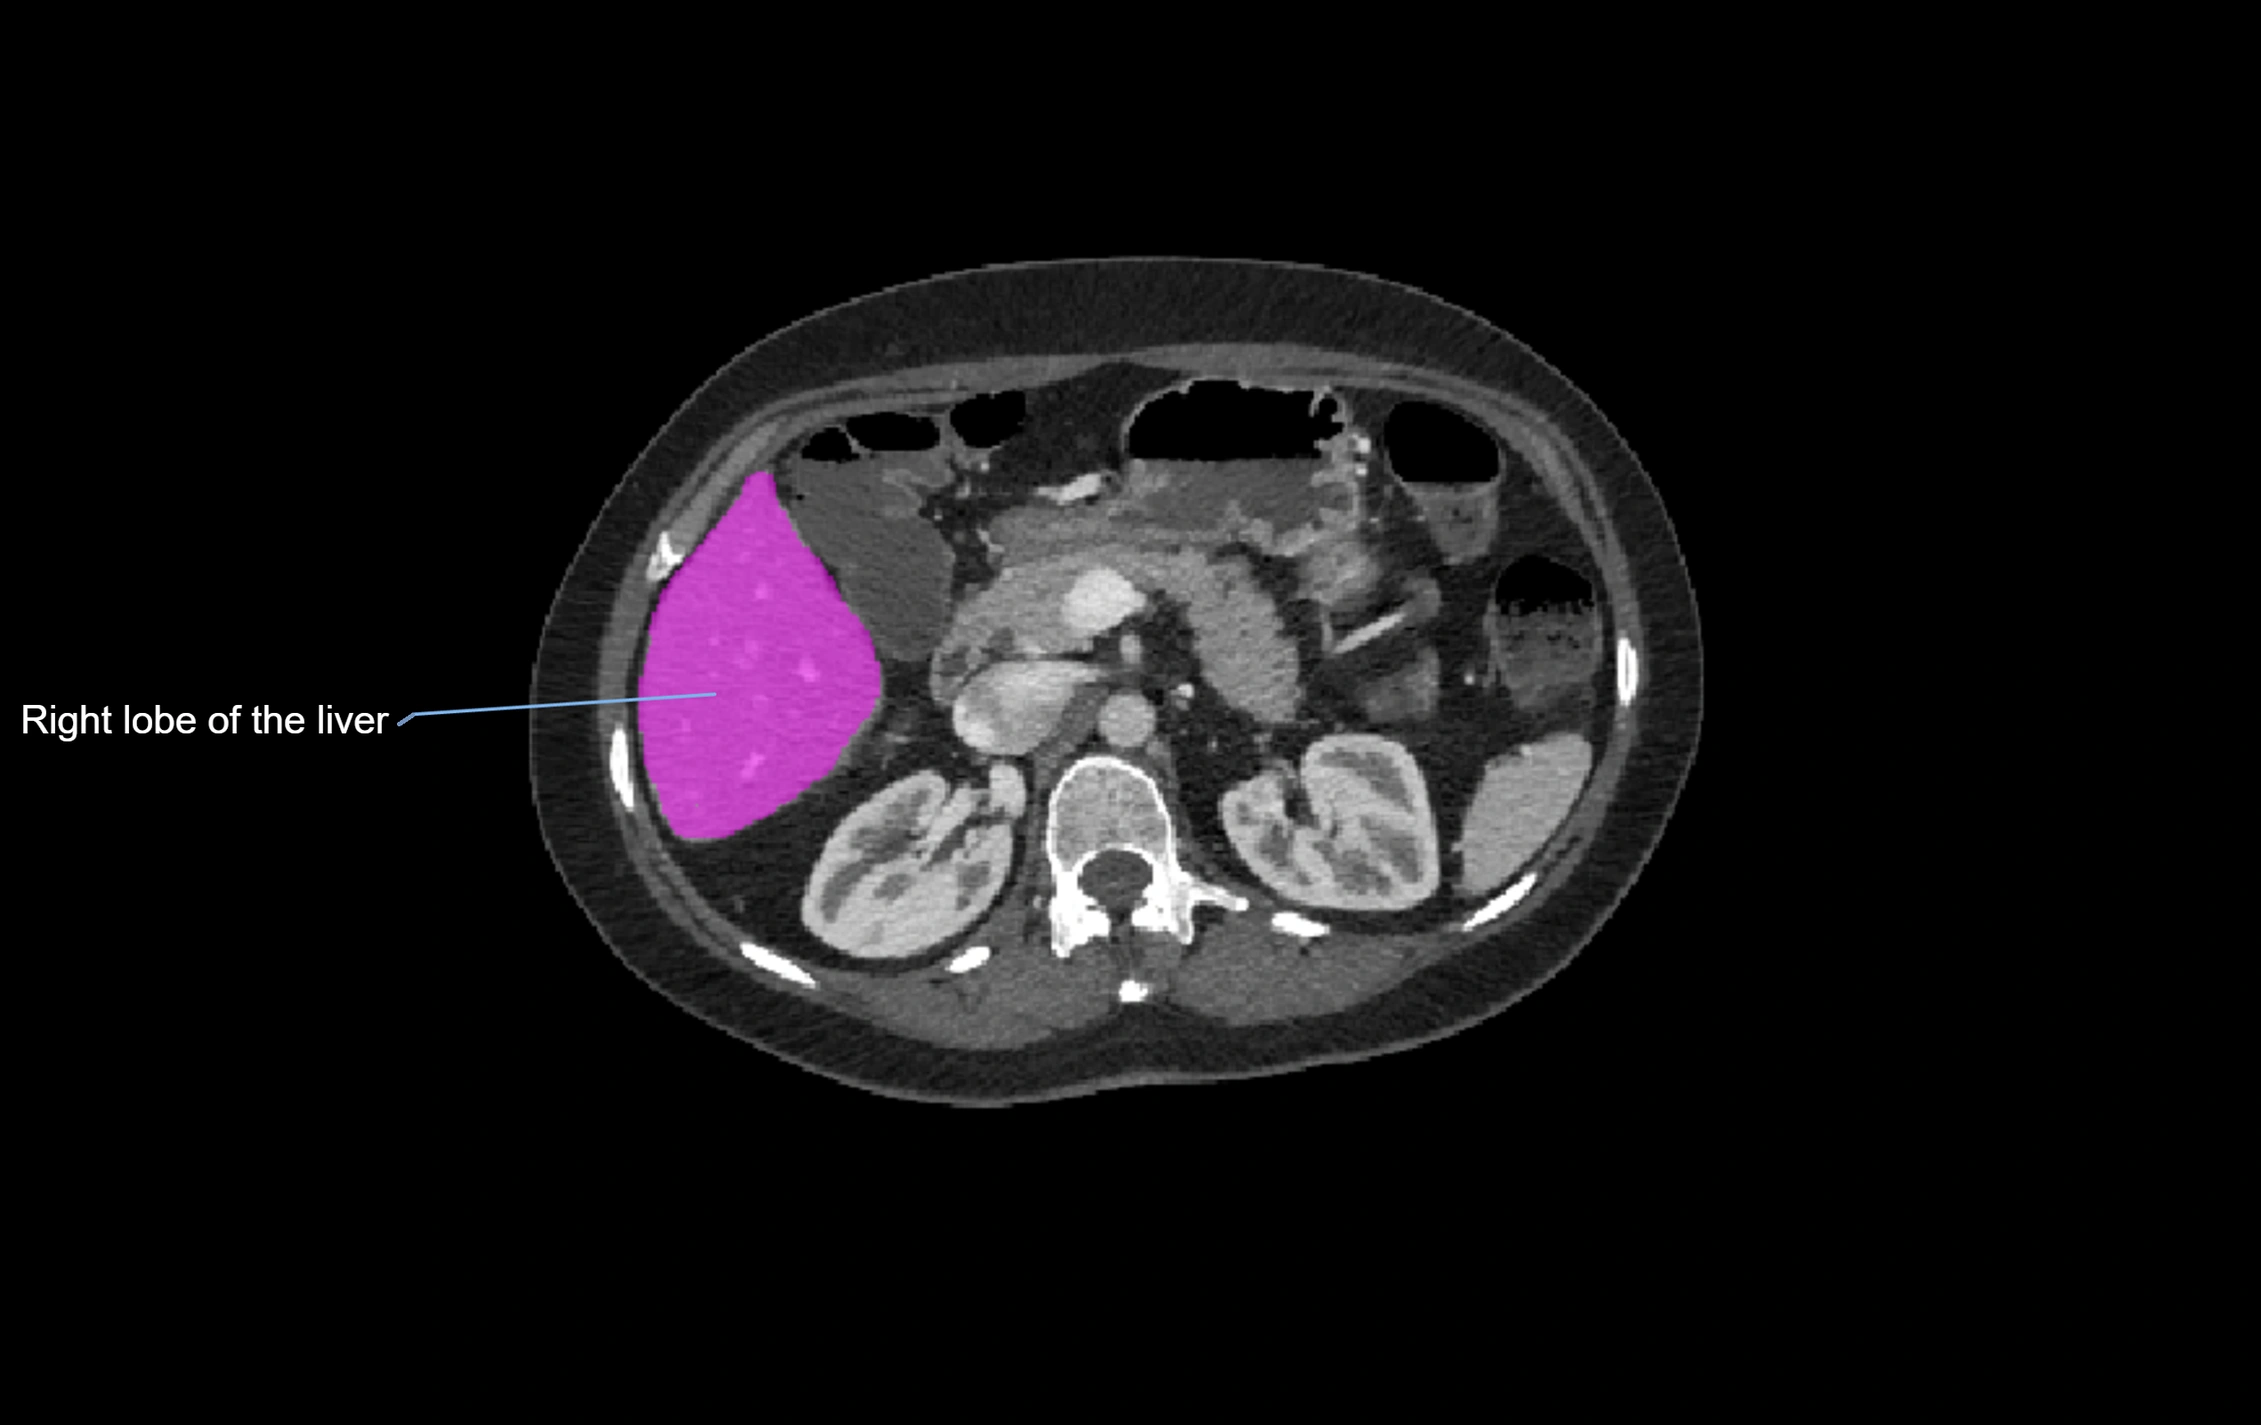

CT Image

image